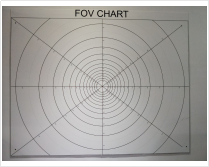

| 視場角 | 視場角靶標 |  | YY 1028-2008YY0068.1-2008 | |

| FDA認證-視場角 | 角度型視場角 |  | FDA認證 | 測量視場角 | |